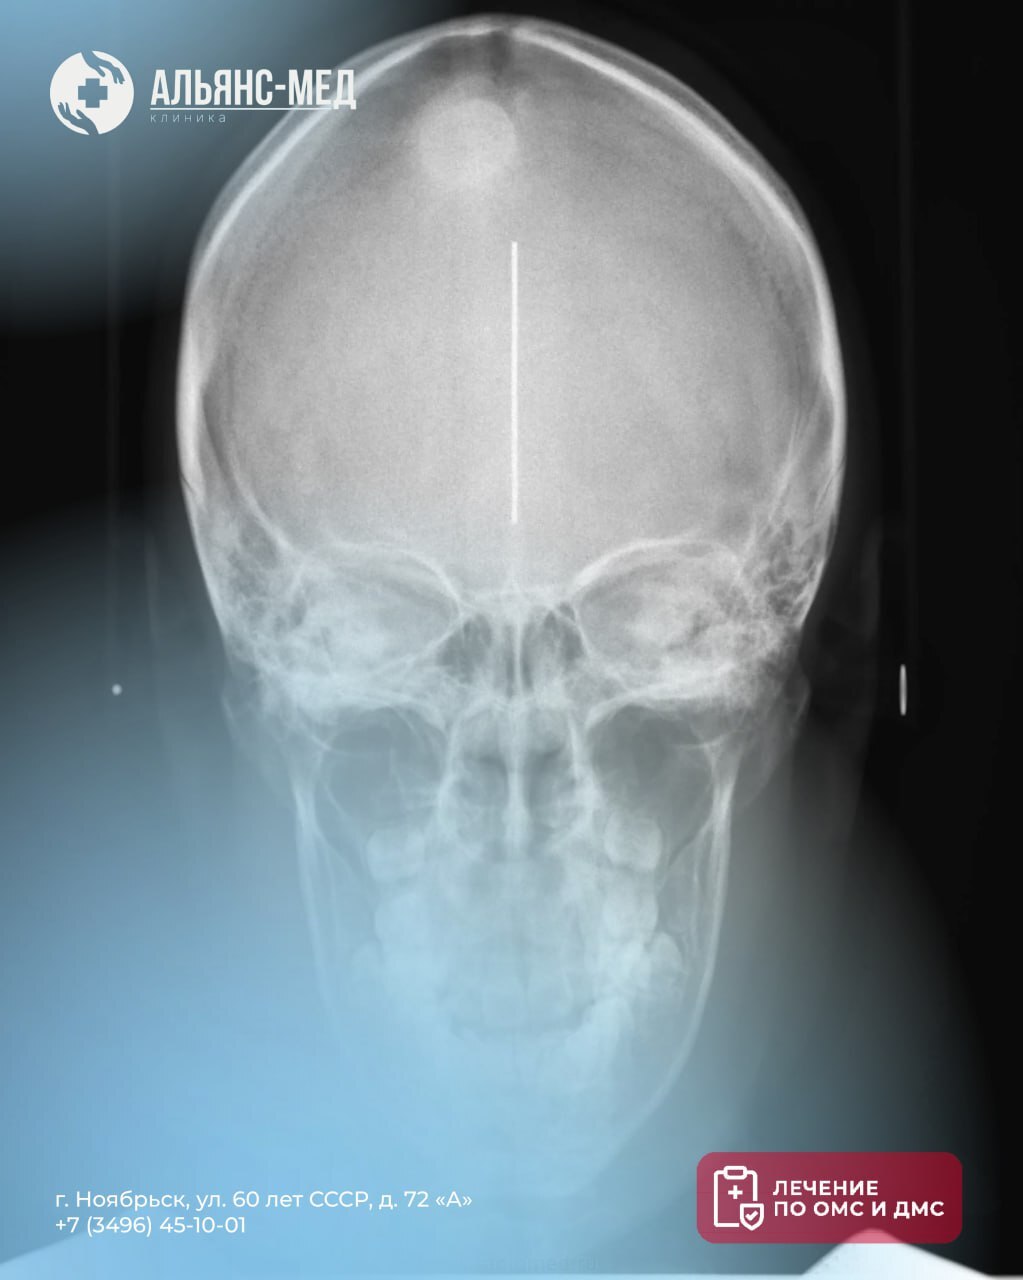

Рентгенография черепа — это простой и надежный способ оценить состояние костных структур.

В каких случаях стоит пройти исследование:

· После травм: ударов, падений, аварий для проверки на переломы

· При постоянных головных болях неясного происхождения

· Для выявления воспалений, таких как синусит

· При подозрении на новообразования или врожденные аномалии

· Для контроля процесса заживления после лечения